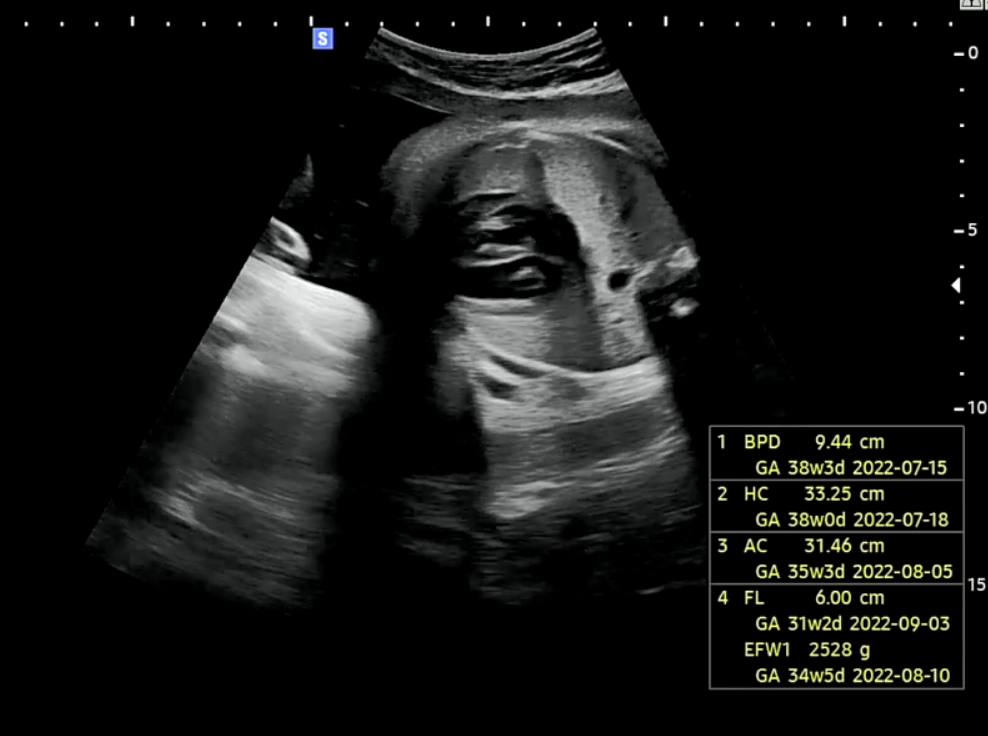

33주차 2일 호띵이 성장 상태

1. BPD, HC (태아 머리크기) = 38주차 3일 태아의 머리크기로 저번 진료대비 1주 더 빠르게 성장했다.

2. AC (복부둘레) = 35주 3일 태아의 복부둘레로 저번 진료와 동일한 속도로 성장하고 있다.

3. FL (허벅지길이) = 31주 2일 태아의 허벅지길이로 저번 진료대비 1주 더 빠르게 성장했다.

4. EFW1 (태아 몸무게) = 34주 5일 태아의 몸무게로 저번 진료대비 1주 더 빠르게 성장했다.

머리크기가 예상보다 더 빠르게 성장하고 있어 자연분만 시 나오다가 머리가 낄 수 있다는 의사선생님의 말에 우리부부는 제왕절개를 고민하는 중이다. 처음부터 자연분만에 대한 로망이나 꼭 자연분만을 해야겠다는 생각이 없었기도 했고 혹시나 나오다가 응급 제왕하는게 더 힘들것 같아서 처음부터 제왕절개를 선택하는 것도 나쁘지않다고 생각하고 있었기 때문이다.